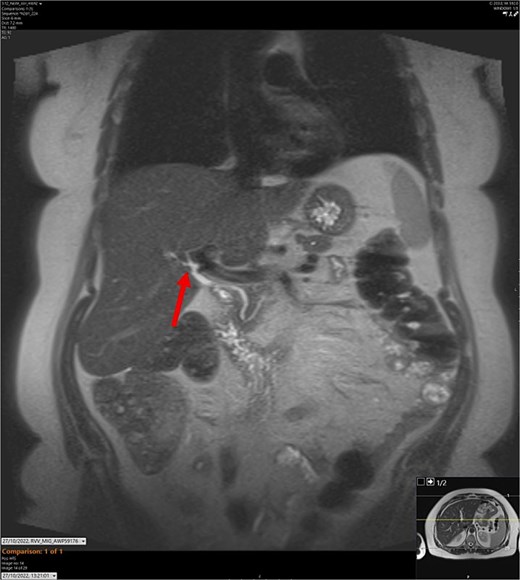

T2-weighted MRCP scan in coronal view. The arrow points to where we expect the gallbladder to be seen, but it cannot be visualized on the scan.

On admission, the patient’s blood tests showed normal inflammatory markers, liver function markers, and amylase (Table 1). The patient underwent an abdominal ultrasound scan, which did not visualize gallstones or the gallbladder. A computerised tomography (CT) abdomen-pelvis scan was done, and the gallbladder could not be visualized (Figs 1 and 2). Further investigations, which include a magnetic resonance cholangiopancreatography (MRCP) and hepatobiliary iminodiacetic acid (HIDA) scan, confirmed a gallbladder bud with an intact biliary tree (Figs 3–6). The patient denied a history of a cholecystectomy. She was diagnosed with gallbladder agenesis.